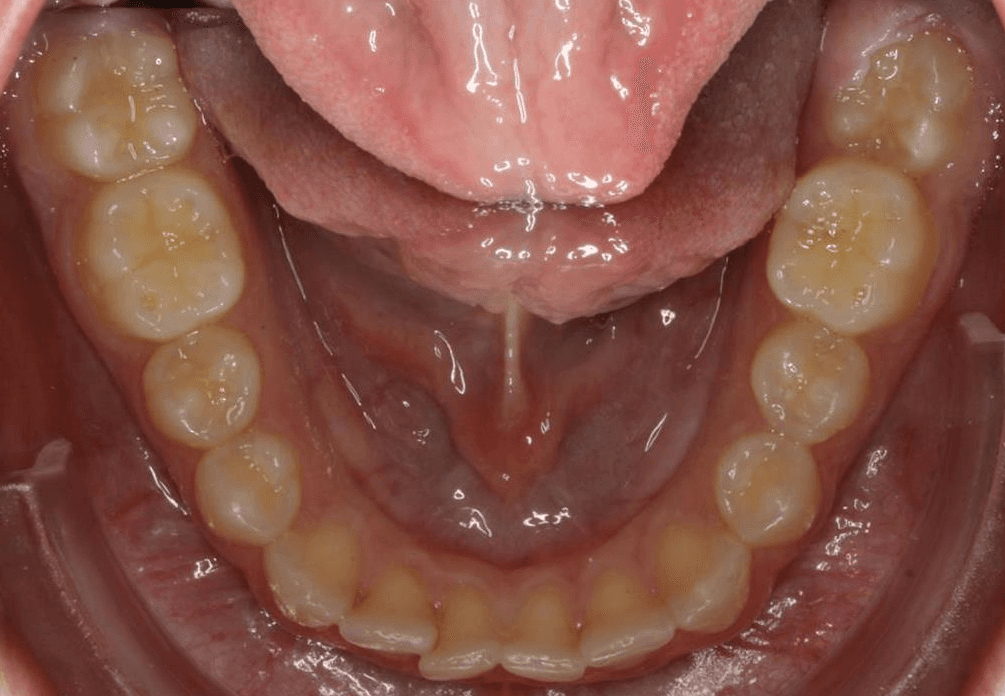

Diganosis: Lower anterior crowding, mild maxillary spacing, misalignment of anterior teeth, rotated premolars and molars

INTRAORAL